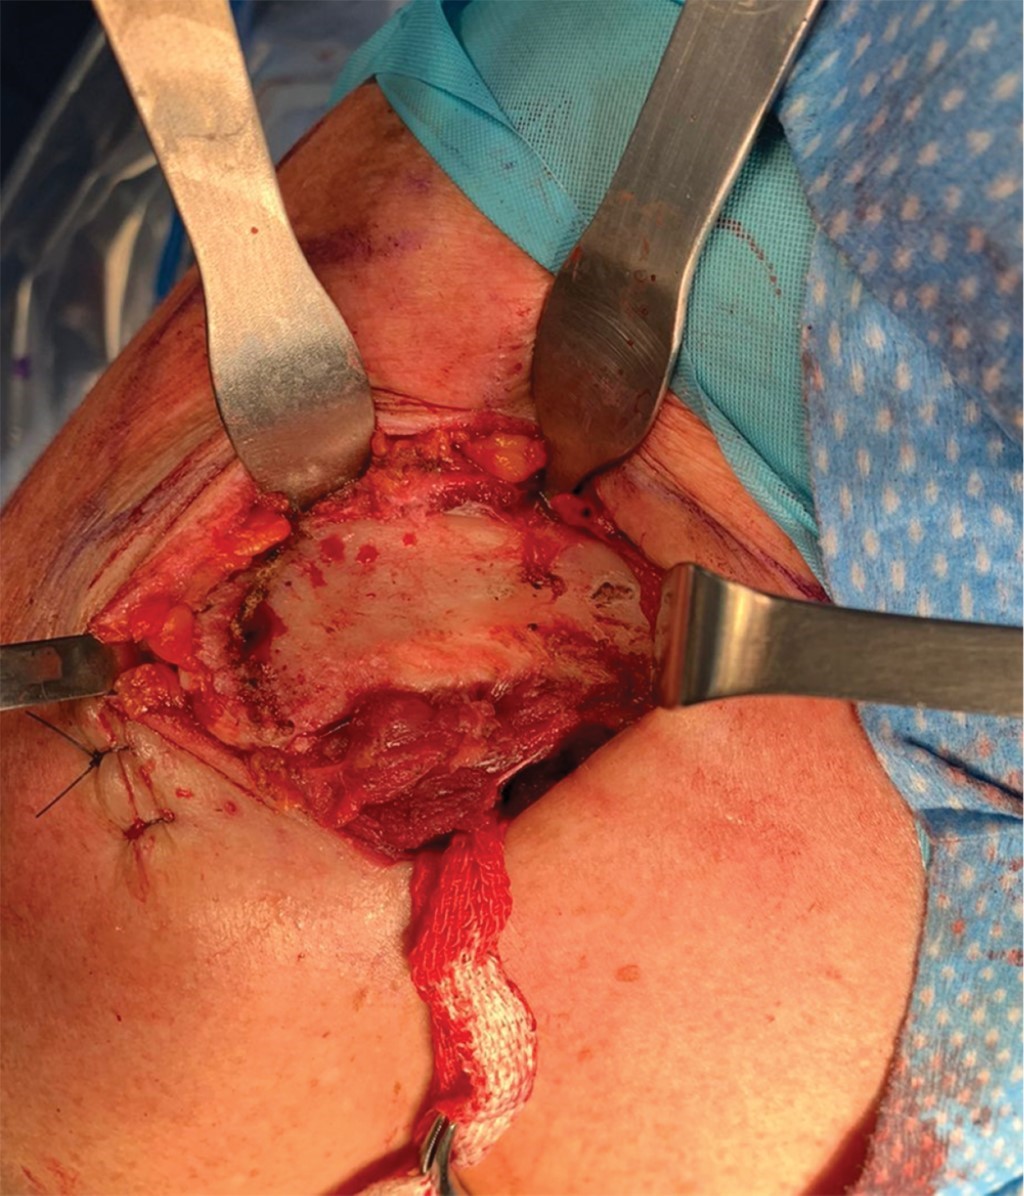

Con el paciente bajo anestesia general balanceada y previa profilaxis antibiótica, se le coloca en posición de silla de playa a 60o de flexión. Por anatomía de superficie se identifican referencias anatómicas: apófisis coracoides, acromion y la articulación AC (Figura 2). Se realiza una incisión en el borde anterior de la clavícula de 5 cm lateral a la articulación AC y se extiende hacia la apófisis coracoides siguiendo las líneas de Langer. Se diseca por planos realizando hemostasia con electrocauterio hasta identificar el músculo deltoides en la parte anterior de la clavícula y la inserción del trapecio en su cara posterior; se realiza disección roma del fascículo deltoideo en dirección a la apófisis coracoides hasta localizar la base de ésta y se pasa una gasa estéril como referencia. Se realiza exposición completa de clavícula y de articulación AC así como de sus tejidos blandos que impiden la reducción articular (Figura 3). Se resecan 3 mm del borde distal de la clavícula y se retiran tejidos blandos (remanente de ligamentos AC y disco articular) (Figura 4).

Figura 1

Figura 4